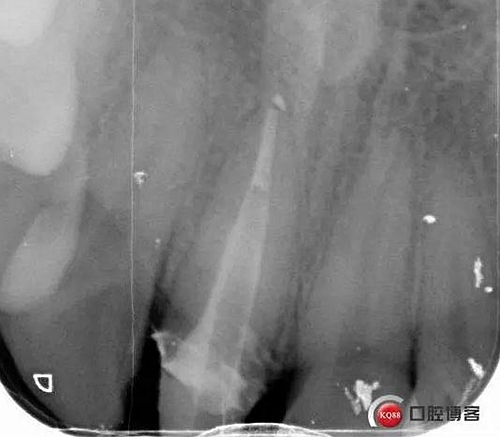

看起來(lái)有點(diǎn)頭痛哈,拍片檢查

牙根長(zhǎng)度比較號(hào),根充完善。這張片子也可以看出,為什么上次脫落了,樁的深度不夠,而且明顯樁根樁道不匹配,打的樁都沒有到位。